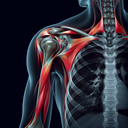

МРТ плечового суглобу

Магнітно-резонансна томографія (МРТ) плечового суглобу – це неінвазивний метод обстеження, який дозволяє отримати детальні зображення м'яких тканин, кісток та суглобів. Він особливо корисний для діагностики травм, розривів зв'язок, запальних процесів та захворювань, таких як артрит. ### Переваги МРТ: - **Безпечність:** Використовує магнітні поля і радіохвилі, без іонізуючого випромінювання...